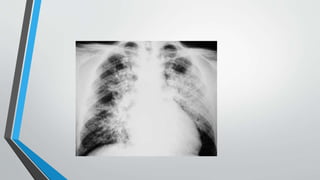

La insuficiencia cardiaca se define como la incapacidad del corazón para bombear sangre a una velocidad y cantidad adecuadas. Las causas afectan primero al ventrículo izquierdo y luego al derecho, resultando en insuficiencia ventricular. La radiología puede detectar signos de cardiomegalia, edema pulmonar, derrame pleural y patrón de "alas de mariposa". El índice cardiotorácico mide el grado de cardiomegalia y es útil para el diagnóstico de insuficiencia cardiaca.